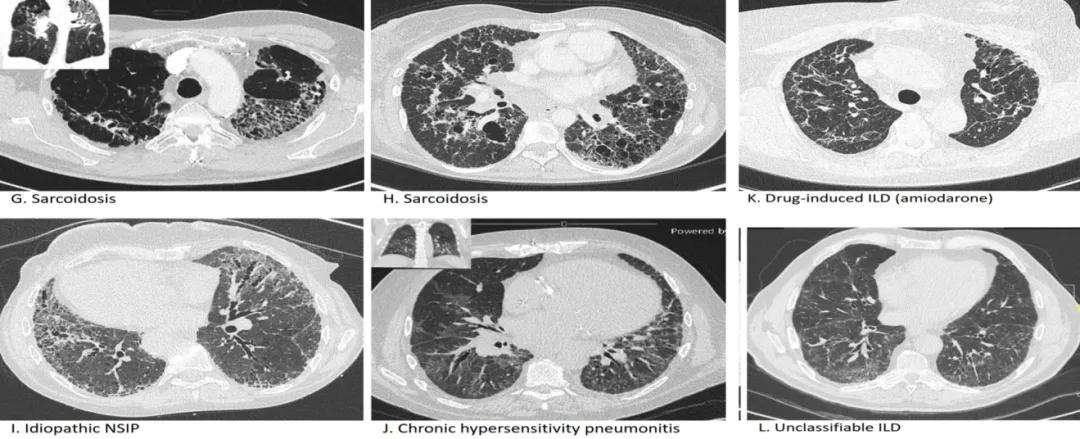

纤维化性ILD的HRCT表现 [24] :

(来源:Wijsenbeek M, Cottin V. Spectrum of fibrotic lung diseases. N Engl J Med 2020;383:958-68.)

这些影像是系统性硬化症、抗合成酶综合征、类风湿关节炎引起等不同类型疾病导致纤维化的HRCT表现。